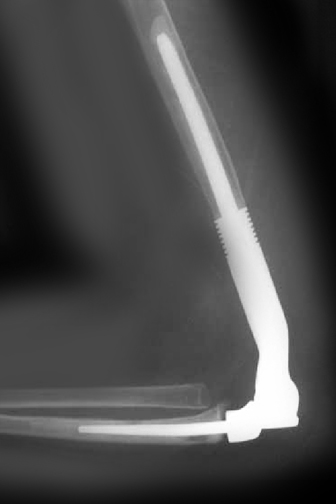

Total Elbow Replacement

Elbow joint replacement, also referred to as total elbow arthroplasty, is an operative procedure to treat the symptoms of arthritis that have not responded to non-surgical treatments.